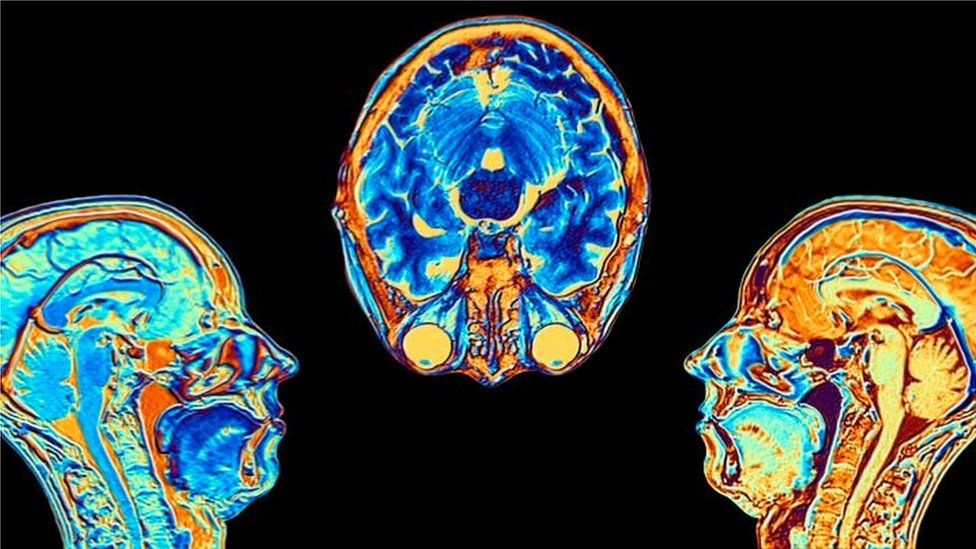

Contagiarse de covid-19 puede provocar cambios en el cerebro, según indicó un estudio publicado en la revista Nature.

Los investigadores hallaron diferencias significativas en las resonancias magnéticas hechas antes y después de la infección.

Incluso después de una infección leve, las imágenes mostraron que el tamaño total del cerebro se había reducido ligeramente, con menos materia gris en las regiones relacionadas con el olfato y la memoria.

• El tamaño general del cerebro en los participantes infectados se había reducido entre un 0,2 y un 2%

• Hubo pérdidas de materia gris en las áreas olfativas, vinculadas al olfato, y en regiones vinculadas a la memoria.